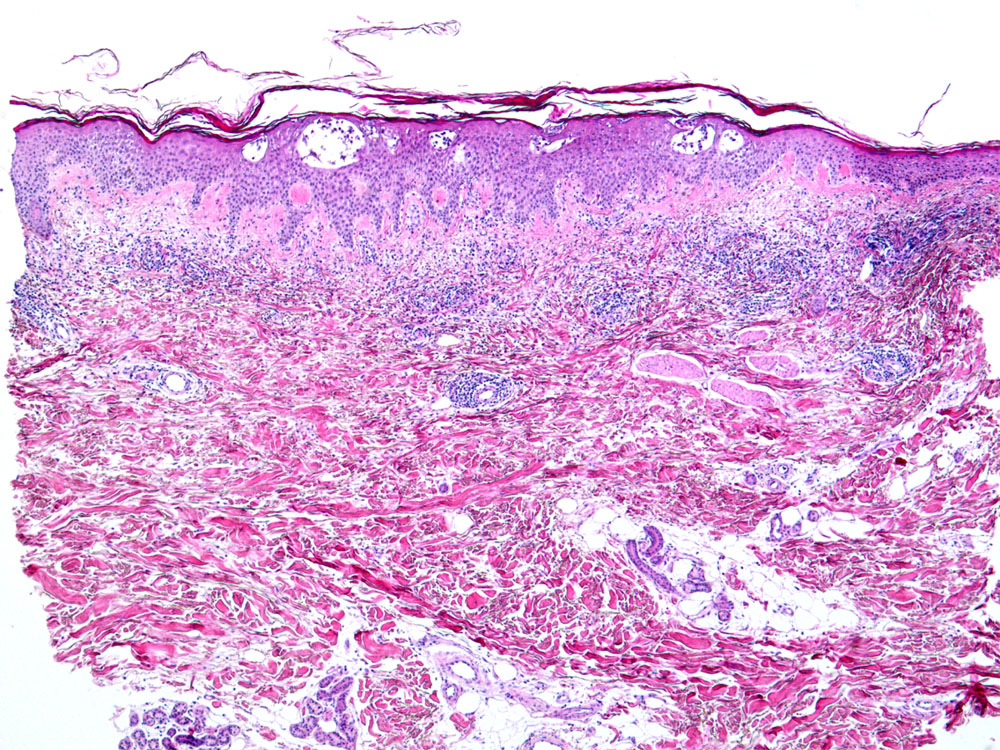

Akute spongiotische Dermatitis vom Ekzemtyp

Geringgradige irreguläre Akanthose der Epidermis. Epidermis und papilläre Dermis erscheinen aufgrund des Ödems relativ hell. Intraepidermale Spongiosebläschen. Schuppenkruste. Oberflächliches perivaskulär betontes Entzündungsinfiltrat.

Randbetonte Rötung mit Infiltration am linken Oberschenkel.

Morphologisch sind die allergische Kontaktdermatitis, das nummuläre Ekzem, die dyshidrotische Dermatitis und die Id Reaktion nicht unterscheidbar. Je nach Stadium unterschiedliche Morphologie.